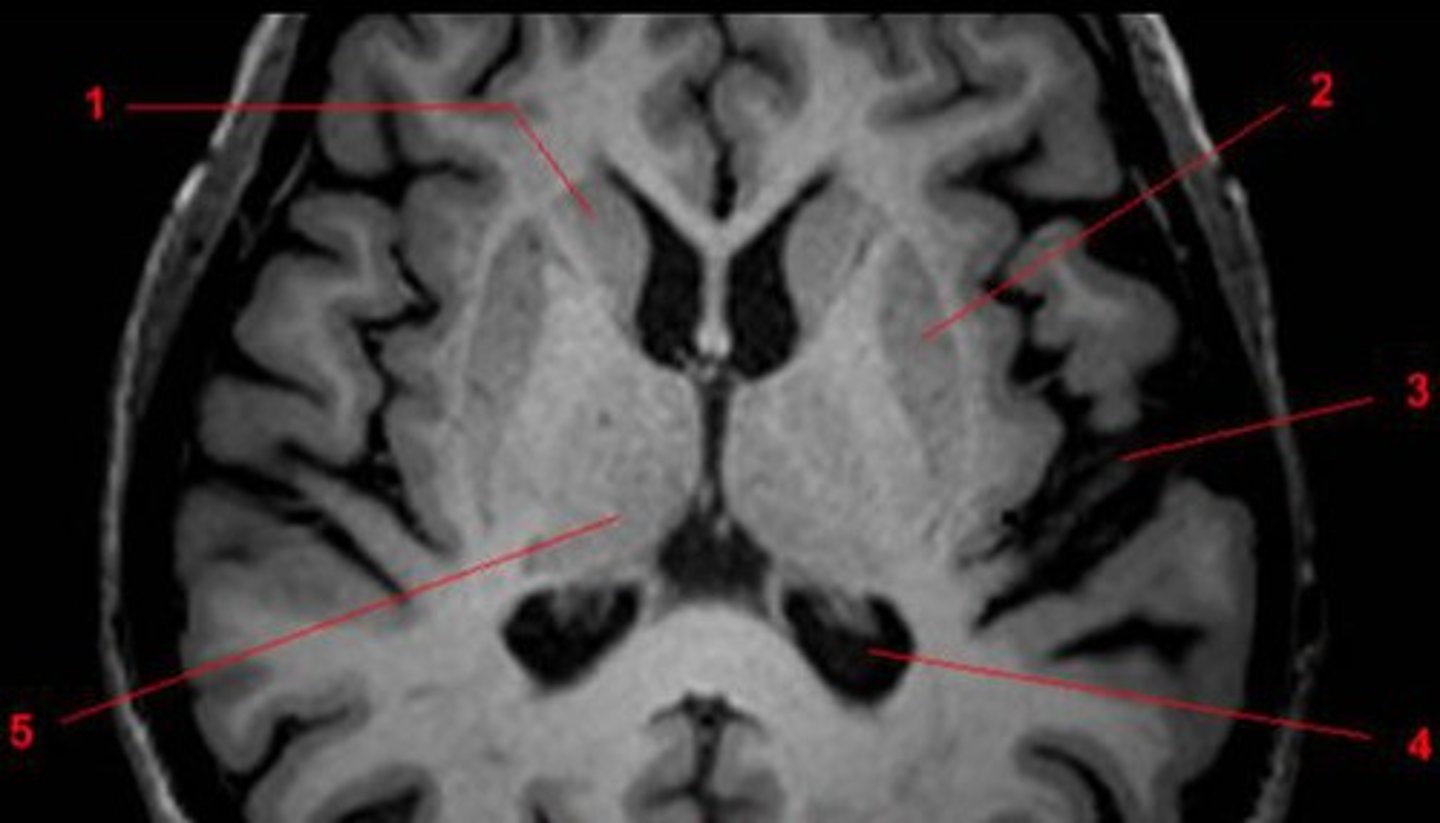

Horizontal or Axial View